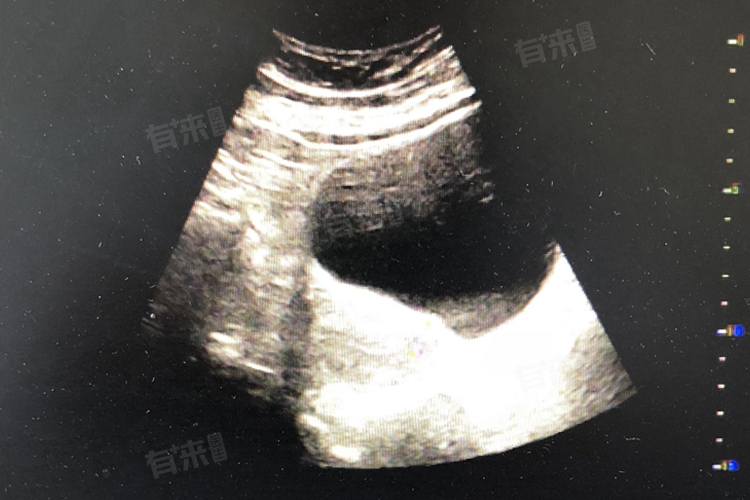

子宫内膜炎是子宫内膜的炎症性疾病,可由细菌、病毒等病原体感染引起,炎症导致子宫内膜充血、水肿,超声检查时可见回声不均匀,甚至伴有宫腔积液,子宫内膜炎若不及时治疗,可能发展为慢性盆腔炎,影响女性生殖健康,需积极抗感染治疗。

子宫内膜增生症是一种非生理性的内膜增殖,可分为单纯性增生、复杂性增生及不典型增生,超声检查时,这些病变均可表现为子宫内膜回声欠均匀,且随着增生程度的加重,回声异常可能更加明显,不典型增生被视为癌前病变,具有较高的恶变风险,需密切随访或手术治疗。

子宫内膜癌是发生在子宫内膜的恶性肿瘤,超声检查时可见子宫内膜增厚、回声不均匀,甚至形成肿块,随着病情进展,肿瘤可侵犯子宫肌层及周围组织,引起一系列严重症状,子宫内膜癌的严重程度最高,需早期诊断、早期治疗以提高生存率。